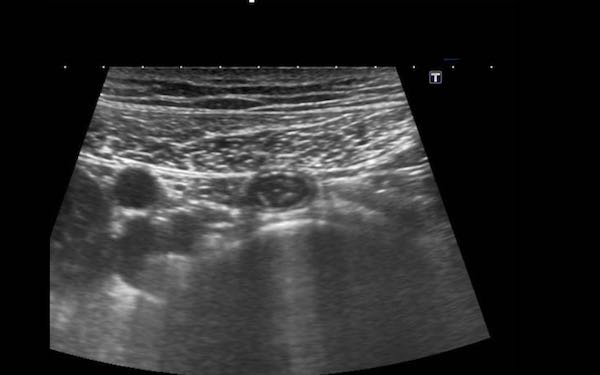

Đây là hình ảnh siêu âm của một trẻ 2 tuổi bị lồng ruột hồi manh tràng từng đợt, được khám trong khoảng thời gian giữa các cơn.

Hồi tràng với nhiều mảng Peyer sa vào manh tràng.

Hình ảnh siêu âm kinh điển của lồng ruột hồi-manh tràng ở hai trẻ khác nhau.

Trong cả hai trường hợp, đoạn hồi tràng bị lồng được định vị không đối xứng bên trong ống lồng ngoài, do mạc treo ruột tăng âm có chứa mỡ, bám vào hồi tràng và đi theo hồi tràng khi bị kéo vào trong.

Trong mạc treo, siêu âm cho thấy một hạch bạch huyết mạc treo (hbh) phóng đại ở cả hai.

Các hạch này phì đại như một phần của tình trạng tăng sản hạch bạch huyết toàn thân và khônghu trú trong lòng hồi tràng.

Do đó đây không phải là điểm dẫn đầu nguyên phát. Ở bệnh nhân bên phải, ruột thừa (mũi tên) cũng bị kéo vào trong.

Lưu ý cấu trúc đa lớp của thành bụng phía trước của phức hợp lồng ruột, đại diện cho ba lớp thành ruột bị gấp lại.